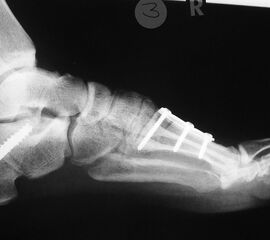

• posttraumatisch (Abb. 5)

• Fuß belastet dp und seitlich (Abb. 14 und 15)

• Saltzman view (Abb. 16)

Typische Merkmale der Standard-Seitaufnahme des Fußes im Stand

• Knöchelgabel ist außen rotiert

• Talus und Calcaneus verlaufen fast parallel

• Sinus tarsi ist einsehbar

• Subtalare Gelenklinie verläuft horizontal und ist breit einsehbar

• Der Abstand Malleolus medialis zum Os naviculare ist verkürzt

• Der Calcaneus erscheint verkürzt

• Der Krümmungsscheitel des Fußes ist erhöht

• Calcaneus pitch ist meist erhöht, der Rückfuß Equinus ist eher selten 12